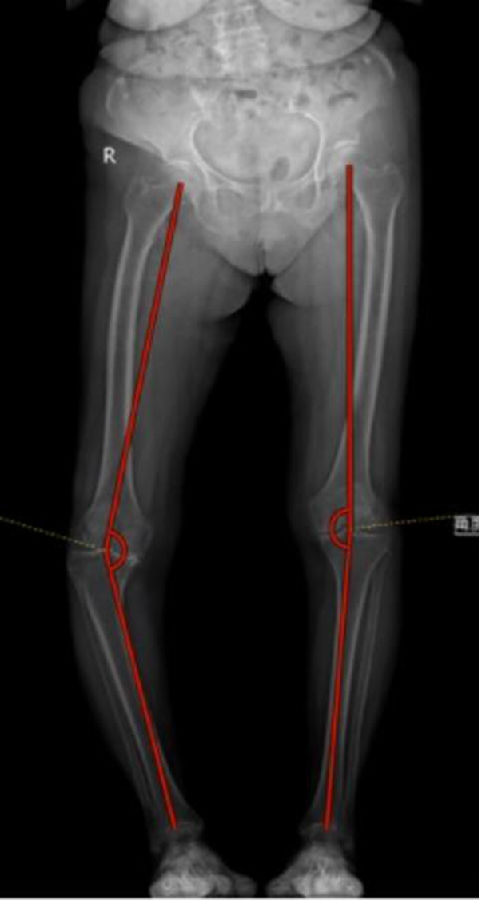

一期双侧内翻膝aMA+arKA典型病例一例。王x,女性,80岁,因“双膝疼痛10余年,加重3月”入院。

PE:双膝内翻畸形,左膝稍肿胀,左膝活动度屈曲100°,伸直0°,内侧关节间隙压痛(+),浮髌试验(-),右膝稍肿胀,活动度屈曲100°,伸直0°,内侧关节间隙压痛(+),浮髌试验(-),双下肢皮肤感觉及末梢血运正常。

手术方案:左侧aMA,右侧arKA

图6图7 术前